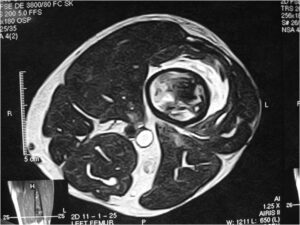

Radiology emulates pathology: Biphasic Tumor

- One region low grade chondrosarcoma

- Second more aggressive area with bone destruction, lysis of calcification, soft tissue mass

- Cortical permeation and a soft tissue mass in 70% of cases

- Or extraosseous soft tissue mass

Characteristically abrupt transition between chondroid tumor and dedifferentiated, lytic component